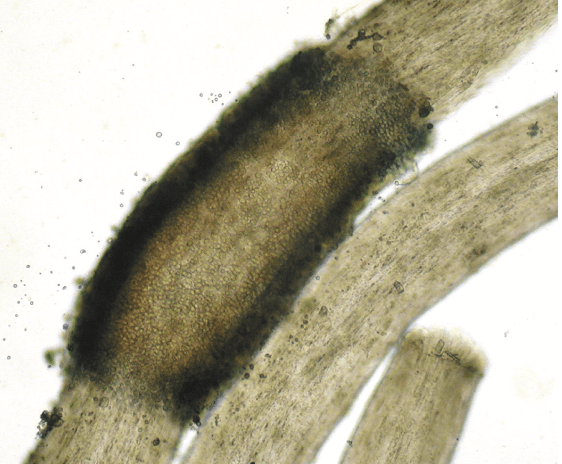

The image depicts a KOH preparation of a nodule on a hair consistent with this entity

What is white piedra?